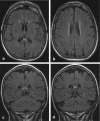

Background and purpose: The splenium of the corpus callosum is the most posterior part of the corpus callosum. Its embryological development, anatomy, vascularization, function, imaging of pathology, possible pathophysiological mechanisms by which pathology may develop and the clinical consequences are discussed.

Methods: A literature-based description is provided on development, anatomy and function. MR and CT images are used to demonstrate pathology. The majority of pathology, known to affect the splenium, and the clinical effects are described in three subsections: (A) limited to the splenium, with elaboration on pathophysiology of reversible splenial lesions, (B) pathology in the cerebral white matter extending into or deriving from the splenium, with special emphasis on tumors, and (C) splenial involvement in generalized conditions affecting the entire brain, with a hypothesis for pathophysiological mechanisms for the different diseases.

Results: The development of the splenium is preceded by the formation of the hippocampal commissure. It is bordered by the falx and the tentorium and is perfused by the anterior and posterior circulation. It contains different caliber axonal fibers and the most compact area of callosal glial cells. These findings may explain the affinity of specific forms of pathology for this region. The fibers interconnect the temporal and occipital regions of both hemispheres reciprocally and are important in language, visuospatial information transfer and behavior. Acquired pathology may lead to changes in consciousness.